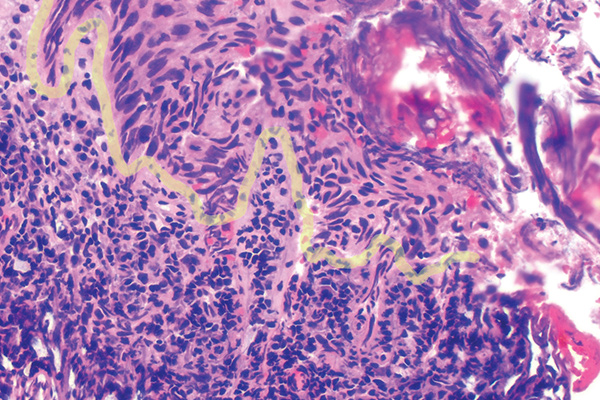

In Figure 1 through Figure 6, a variety of tissue biopsies collected via laser excision are presented. Figure 1 demonstrates the potential cellular distortion to the basement membrane region precluding detection of premalignant change. Figure 2 through Figure 4 highlight the cauterization and separation artifact caused in part by use of continuous wave versus pulsed mode. Figure 5 and Figure 6 demonstrate that by employing the advantages of laser surgical biopsy, it is possible to cleanly collect the specimen while preserving the marginal integrity of the area of suspected pathology without distortion.

Laser biopsy causing cellular distortion and disruption of the epithelium and connective tissue interface, highlighted in yellow (810 nm, 2.5 W, 25 Hz, 30 msec pulse, 50% duty cycle).

Fig 1